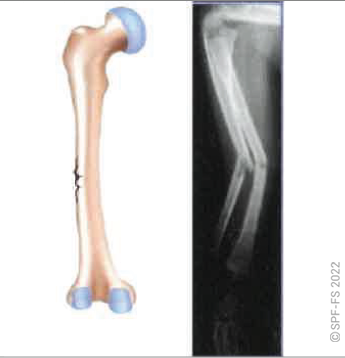

Les membres inférieurs

Les membres inférieurs sont chacun formés de trois segments :

Figure 2-13 : le membre inférieur

La hanche est l'articulation qui relie la cuisse au bassin. Le genou relie la cuisse à la jambe et la cheville la jambe au pied.

Ce dernier comporte cinq orteils numérotés de 1 à 5 de l'intérieur vers l'extérieur. Les phalanges sont numérotées de P1 à P3, dans le sens allant du talon vers l'ongle.